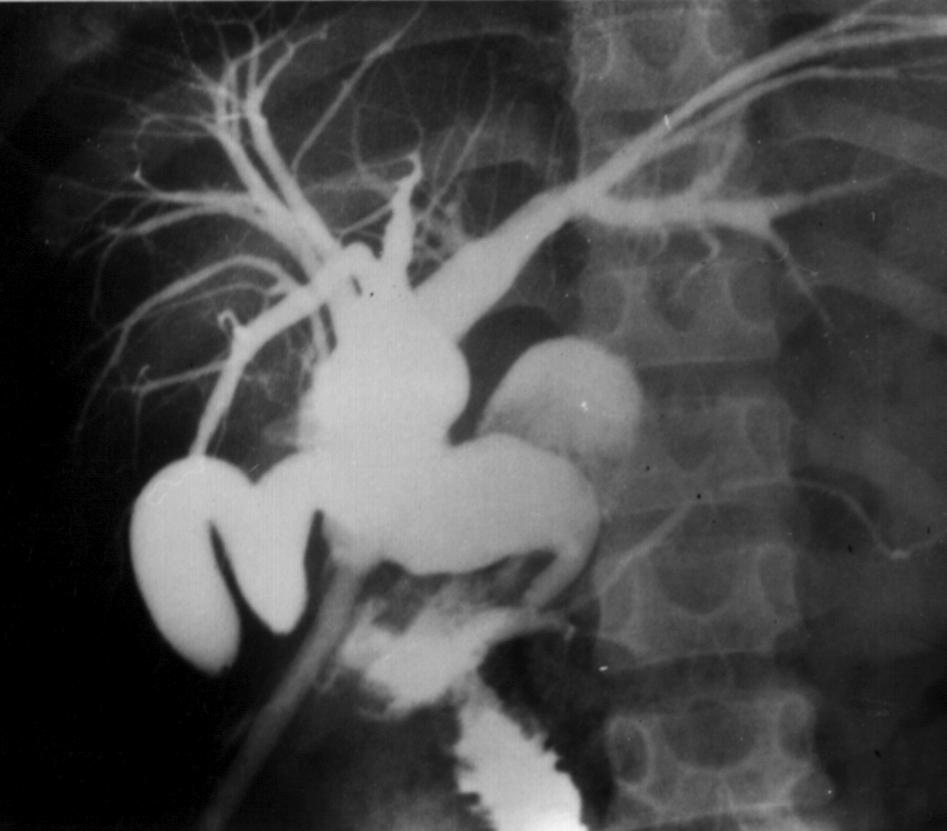

Cbd3.jpg (52524 bytes)